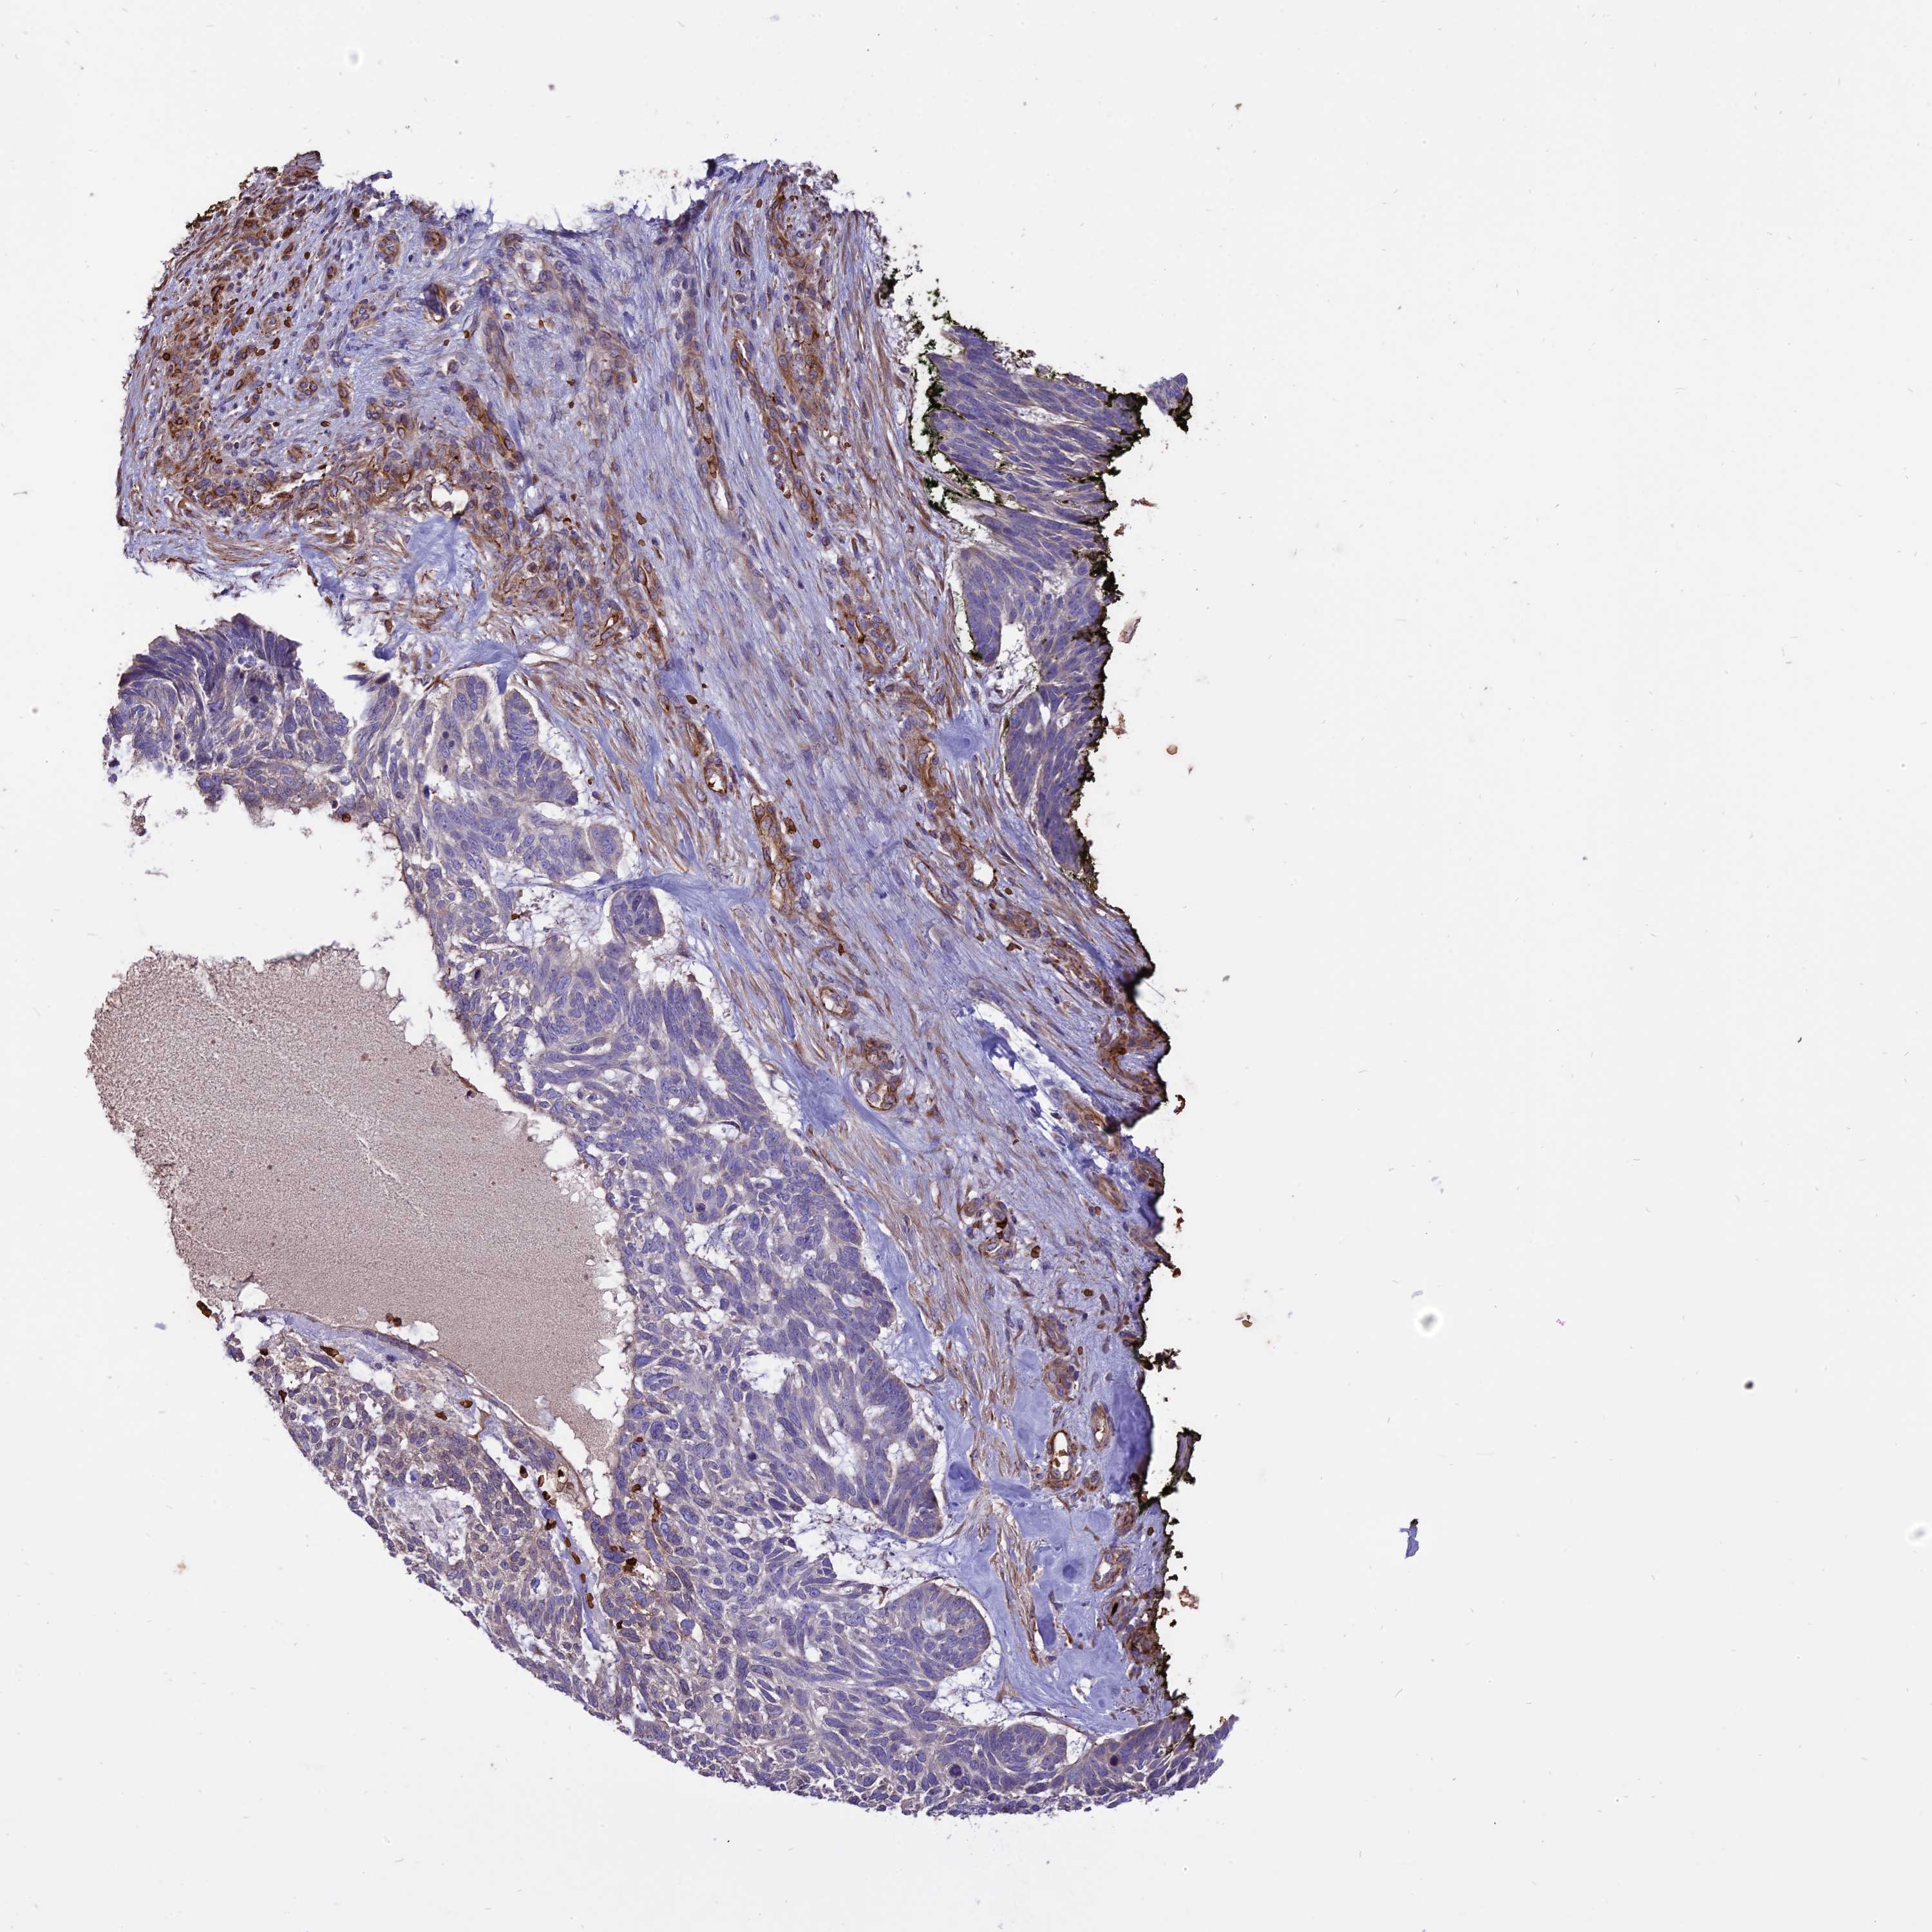

SKIN CANCER - Protein expressioni

A mouse-over function shows sample information and annotation data. Click on an image to view it in a full screen mode. Samples can be filtered based on level of antibody staining by selecting one or several of the following categories: high, medium, low and not detected. The assay and annotation is described here.

Each image is clickable and will lead to virtual microscopy that enables deeper exploration of all samples and also displays staining intensity scores, fraction scores and subcellular localization as well as patient and tissue information for each sample.

Antibody HPA042459

Squamous cell carcinoma, NOS